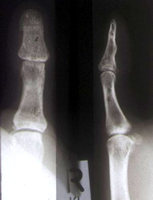

Mittelgliedköpfchenfraktur des kleinen Fingers - Ergebnis nach geschlossener Reposition

Diese schwer zu stabilisierende Köpfchenfraktur läßt sich ohne großen Aufwand mit dem Minifixateur stabilisieren. Die Reposition ist einfach.